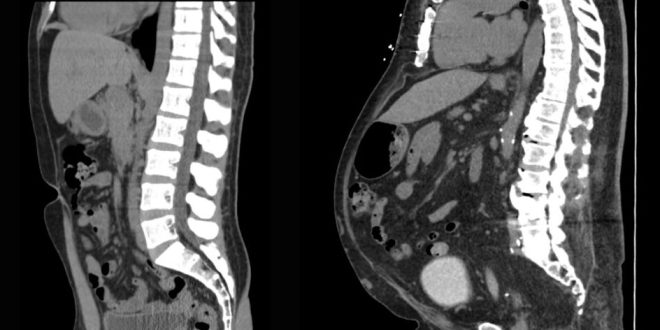

فقط با انجام اسکنهای گرانقیمت میتوان دقیقاً میزان چربی احشایی کرد. اما اگر میخواهید در خانه به طور تقریبی این عدد را به دست آورید، میتوانید از یک متر نواری ساده برای تخمین آن بر اساس اندازه دو کمر خود استفاده کنید.

هیچ راهی برای دانستن دقیق محل و میزان چربی احشایی شما بدون آزمایشهای تصویربرداری گرانقیمت وجود ندارد. بعید است که هرگز فقط برای اندازهگیری چربی بدن خود به این آزمایشها نیاز داشته باشید.